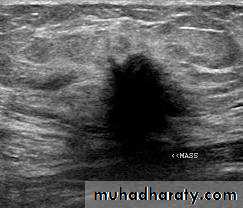

(2)ultrasound: ultrasound is particularly useful in young women with dense breasts in whom mammograms are difficult to interprets, and in distinguishing cysts from solid lesions. It also can be used to localize impalpable areas of breast pathology. It is useful as screening tool and remains operator dependent. Increasingly, ultrasound of the axillary tissue is performed when cancer is diagnosed and guided percutaneous biopsy of any suspicious glands may be performed.

(4) needle biopsy/ cytology: histology can be obtained under local anesthesia using a spring loaded core needle biopsy device. Cytology is obtained using a 21 G or 23G needle and 10 ml syringe with multiple passes through the lump with negative pressure in the syringe. The aspirate is then smeared on to a slide which is air dried or fixed. Fine needle aspiration cytology (FNAC) is the least invasive technique of obtaining a cell diagnosis and is a rapid and very accurate if both operator and cytologist are experienced.

However, false negative do occurs, mainly through sampling error, and invasive cancer cannot distinguished from in situ disease. A histological specimen taken by a core biopsy allows a definitive preoperative diagnosis, differentiates between duct carcinoma in situ and invasive disease and also allows the tumor to be stained for receptor status.

This is important before commencing neoadjuvant therapy. (5)large needle biopsy with vacuum systems: the sampling error decreases as the biopsy volume increases and using 8G or 11G needles allows more extensive biopsies to be taken this is useful in management of micro calcifications or in complete excision of benign lesions such as fibroadenomas.